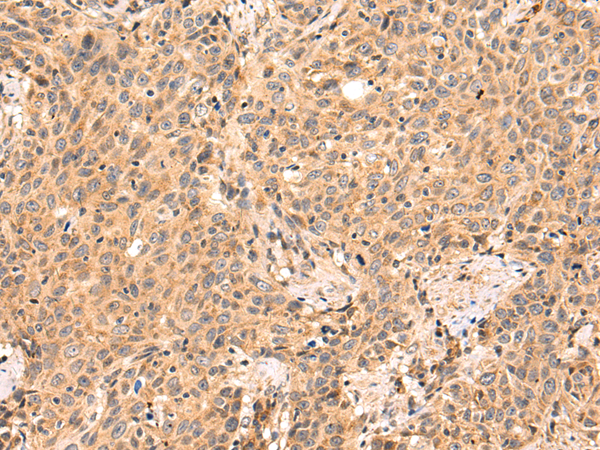

IHC positive control: |

Human prostate cancer and Human colorectal cancer |